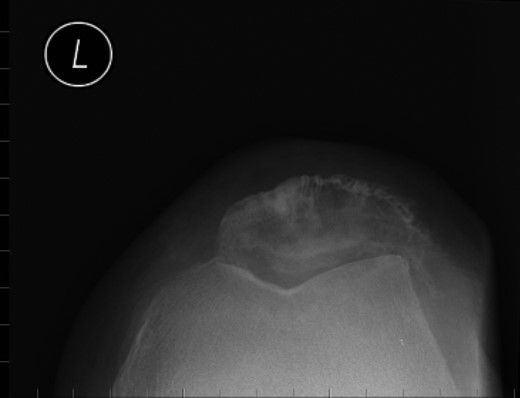

Nineteen months earlier the patient had consulted his general practitioner complaining of left knee pain. Radiographs performed at that time were reported to show joint space narrowing within the patello-femoral compartment as well as early joint space narrowing within the medial compartment. A subchondral lucency was also noted within the patella which was described as a subarticular cyst secondary to the previously mentioned patello-femoral degeneration (Figs 1–3).

Repeat radiographs performed by his general practitioner 19 months after initial presentation (Figs 4–6) revealed a large lucency within the patella and a discontinuity in the anterior cortex of the inferior pole suggesting pathological fracture. A bone scan was arranged and demonstrated isolated abnormal tracer activity around the left patella (Fig. 7). Due to the pacemaker a computed tomography (CT) scan was performed to further characterize the lesion. This confirmed a large lucent area occupying most of the patella with multiple areas of cortical disruption along its anterior border (Fig. 8). Since the exact nature of the lesion could not be determined an ultrasound-guided biopsy was suggested but ultrasound screening revealed the lesion to be highly vascular (Fig. 9). In view of this the radiologist performed a renal ultrasound, which revealed a large mass arising from the superior pole of the left kidney. Subsequent CT of the chest, abdomen and pelvis followed demonstrating the extent of disease. There was a large (13 × 8.5 × 9 cm) mass arising from the superior pole of the left kidney (Fig. 10), the appearances of which were consistent with a primary RCC. Metastases were found in both adrenals and lungs, but no other bone metastases. Since diagnosis, the patient has had a left nephrectomy and is currently receiving radiotherapy and zolendronic acid treatment for the patella metastasis. At the time of writing this report the patient's patella lesion continues to be managed non-operatively.

The absence of associated features of systemic disease, as well as radiographic appearances in keeping with early patello-femoral osteoarthritis (OA), account for the delay in diagnosis. The initial images suggest mild degeneration but, whilst subarticular cysts are a radiographic feature of OA, the lesion shown in this case is larger than would be expected with the level of disease shown elsewhere in the joint.